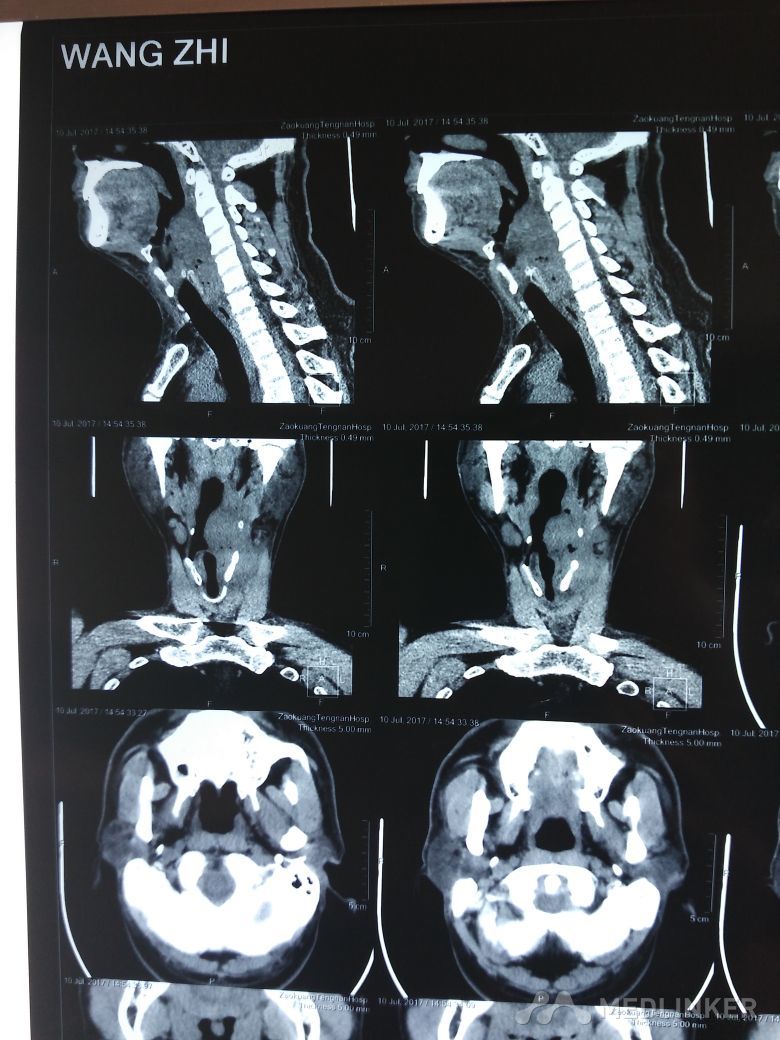

喉肿物

喉部不适半年。与半年前丝杆后部不适症状,近一个月来症状加重,并且伴有声音嘶哑,经过喉部ct检查,发现喉部新生物生长

。